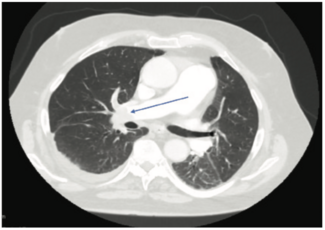

Clot in transit, a rare, life-threatening condition usually associated with pulmonary embolism, is a free-floating thrombus found on the right side of the heart waiting to embolize.